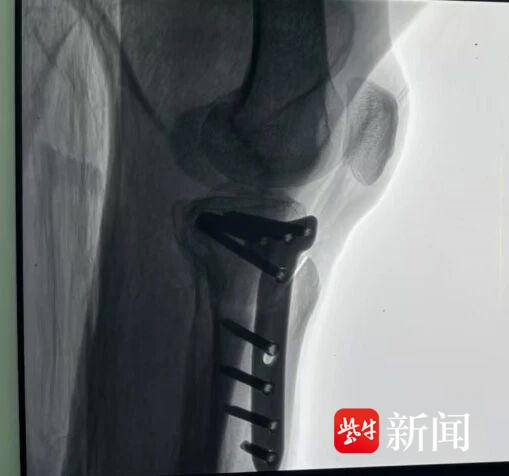

高师傅很快办理了住院手续,积极配合各项术前检查与准备工作。在完善术前评估后,袁永建、石铸等在手术部的协同下为高师傅实施了左胫骨高位截骨手术(HTO)。关节镜下可见患者半月板损伤严重。团队凭借精湛的技术和丰富的经验,精准地完成了截骨、矫正等关键步骤,手术过程十分顺利,约1小时完成,几乎没有出血。

通过手术改变膝关节行走受力点。通讯员供图